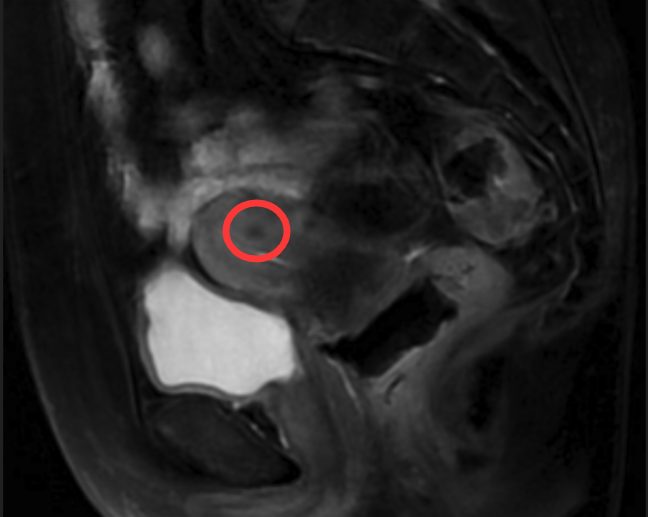

治疗过程:患者因下腹剧痛就医,经医师诊断及各项检查,影像磁共振检查显示盆腔占位,确诊为卵巢囊肿蒂扭转。妇科陈建国主任综合考虑患儿各方面因素后,与家属充分沟通,决定实施 “单孔腹腔镜卵巢囊肿剔除术”。手术顺利完成,术后蓉蓉恢复良好。单孔腹腔镜手术仅在肚脐部留下不到 2 厘米的小伤口,隐蔽不易察觉。术后 3 天,蓉蓉达到出院标准,顺利出院。